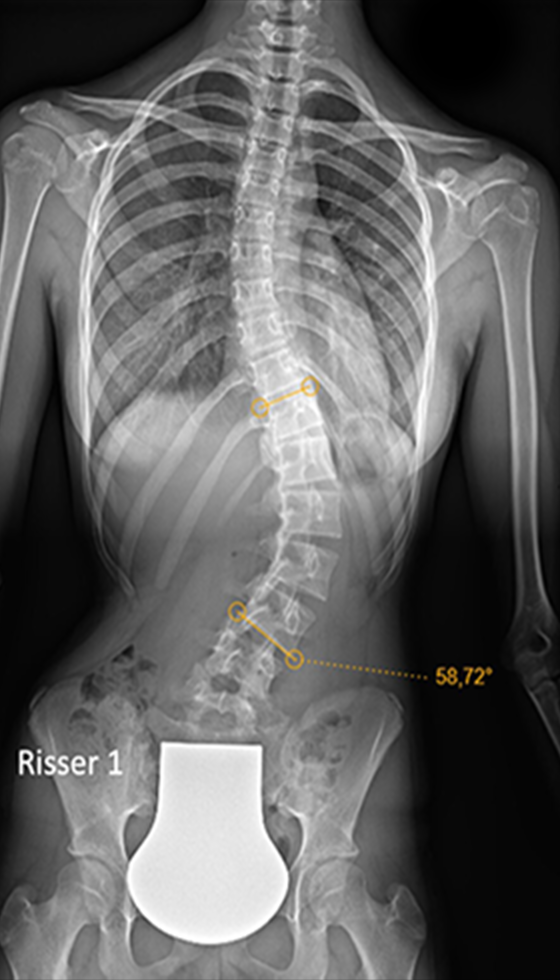

Gallery : Before - After